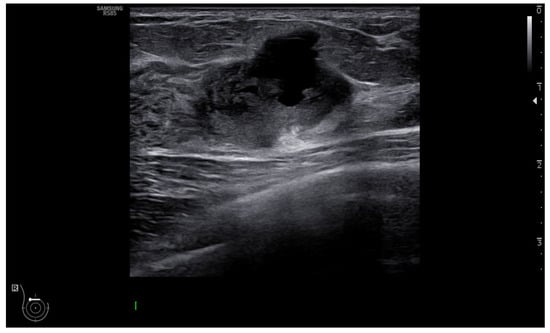

- Guo, Y.; Hu, Y.; Qiao, M.; Wang, Y.; Yu, J.; Li, J.; Chang, C. Radiomics Analysis on Ultrasound for Prediction of Biologic Behavior in Breast Invasive Ductal Carcinoma. Clin. Breast Cancer 2018, 18, e335–e344. [Google Scholar] [CrossRef]

- Luo, W.Q.; Huang, Q.X.; Huang, X.W.; Hu, H.T.; Zeng, F.Q.; Wang, W. Predicting Breast Cancer in Breast Imaging Reporting and Data System (BI-RADS) Ultrasound Category 4 or 5 Lesions: A Nomogram Combining Radiomics and BI-RADS. Sci. Rep. 2019, 9, 11921. [Google Scholar] [CrossRef]

- Xiong, L.; Chen, H.; Tang, X.; Chen, B.; Jiang, X.; Liu, L.; Feng, Y.; Liu, L.; Li, L. Ultrasound-Based Radiomics Analysis for Predicting Disease-Free Survival of Invasive Breast Cancer. Front. Oncol. 2021, 11, 621993. [Google Scholar] [CrossRef]

- Yu, F.; Hang, J.; Deng, J.; Yang, B.; Wang, J.; Ye, X.; Liu, Y. Radiomics features on ultrasound imaging for the prediction of disease-free survival in triple negative breast cancer: A multi-institutional study. Br. J. Radiol. 2021, 94, 20210188. [Google Scholar] [CrossRef]

- Dasgupta, A.; Bhardwaj, D.; DiCenzo, D.; Fatima, K.; Osapoetra, L.O.; Quiaoit, K.; Saifuddin, M.; Brade, S.; Trudeau, M.; Gandhi, S.; et al. Radiomics in predicting recurrence for patients with locally advanced breast cancer using quantitative ultrasound. Oncotarget 2021, 12, 2437–2448. [Google Scholar] [CrossRef] [PubMed]